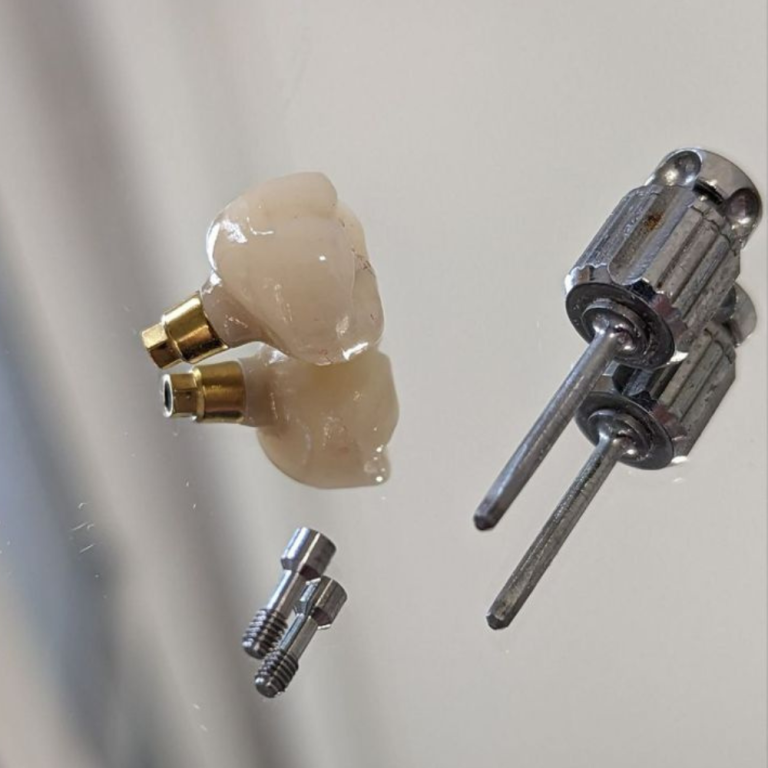

Se enfoca en la reposición de dientes perdidos mediante implantes dentales (raíces artificiales de titanio) que se integran al hueso.

- Prótesis sobre implantes